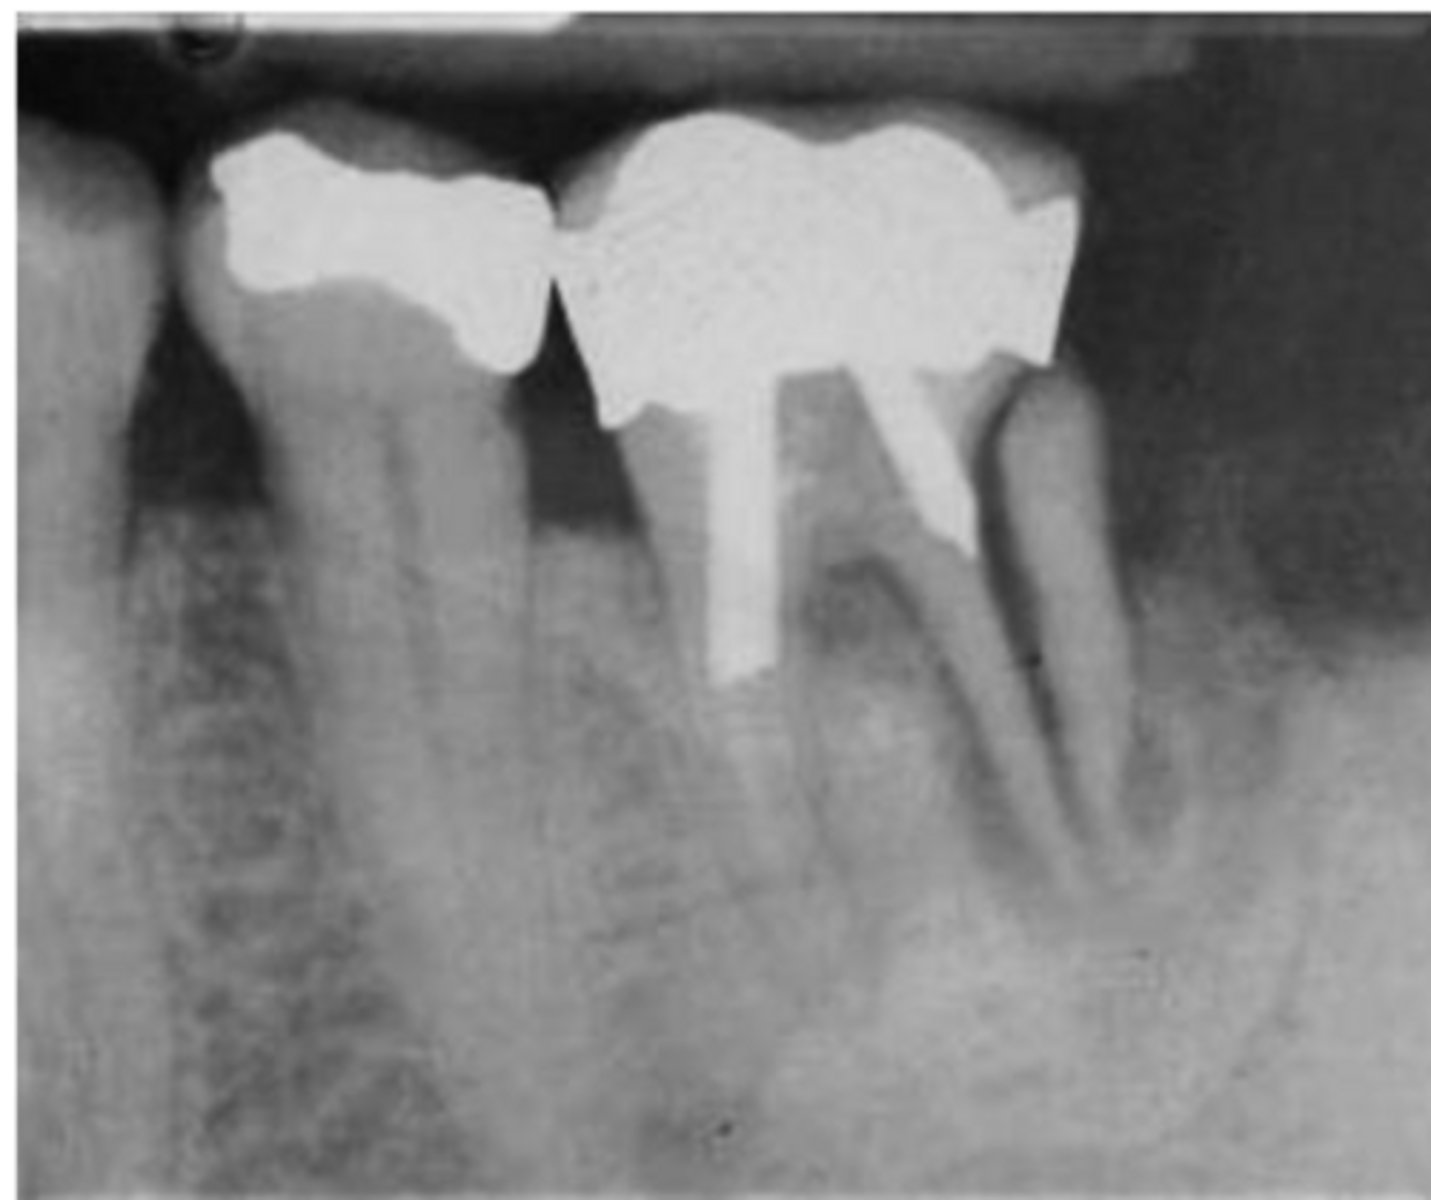

What are the radiographic findings on #19?

- Crown

- PARL in Mesial and Distal Root

- Discontinuation of LD

What are the radiographic findings on #4?

- DO Composite

- RCT

- No PARL

- LD intact

- PDL normal